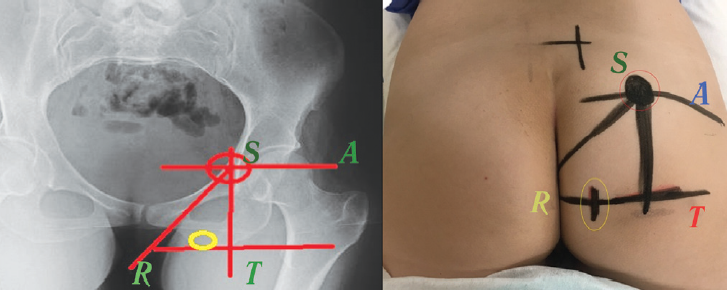

The pudendal nerve trunk is short, and it enters the pelvic area from the sub-piriform space and then passes through the pudendal canal, at the exit of which it branches. Thus, the main place where the nerve trunk can be influenced corresponds to its location next to the sciatic spine of the sciatic bone. The marking for electrode implantation in this area was also performed under X-ray control according to the STAR method (spine, tuberosity, acetabulum, and analrim) [9]. Initially, on the implantation side of the electrode, the middle of the acetabulum was determined, which corresponds to point A. A horizontal line was drawn on the skin through point A with a marker. Then, the point T corresponding to the middle of the lower edge of the ischial tuberosity was determined. A vertical line was drawn through the point T perpendicular to the first one. The intersection of these lines (point S) corresponds to the sciatic spine, which is also visible in the oblique image (with an approximately 15–30° angle of inclination), because in a strictly direct projection it is overlapped with the hip joint or branch of the sciatic bone. From point S, a line was drawn to the outer edge of the anal sphincter (point R). After the points T and R were connected, the resulting segment was divided in half. The middle of this segment served as the point for the needle insertion (yellow circle) and the apex of the triangle (point S) was the target for advancing the needle with the electrode (red circle) (Fig. 2).

Fig. 2. Anatomical landmark for implantation of the electrode on the pudendal nerve: Spine (sciatic spine, S), Tuberosity (ischial tuberosity, T), Acetabulum (coxal cavity, A), Analrim (anal sphincter, R) (left) (see explanation in the text). Projection points of the pudendal nerve (red circle) and the location of the skin incision to insert the Tuohi needle (yellow circle) (right)

Рис. 2. Анатомический ориентир для имплантации электрода на половой нерв: Spine (седалищная ость, S), Tuberosity (седалищный бугор, T), Acetabulum (вертлужная впадина, A), Analrim (анальный сфинктер, R) (слева) (см. пояснение в тексте). Разметка маркером точки проекции полового нерва (красный круг) и место разреза кожи для введения иглы Туохи (желтый круг) (справа)